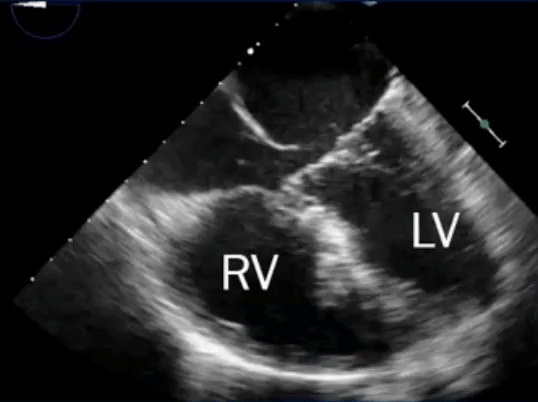

- TEE below shows bicaval view. To identify the superior sinus venosus defect (i.e. SVC type), you’ll want to pay attention to the SVC area as highlighted in this image.